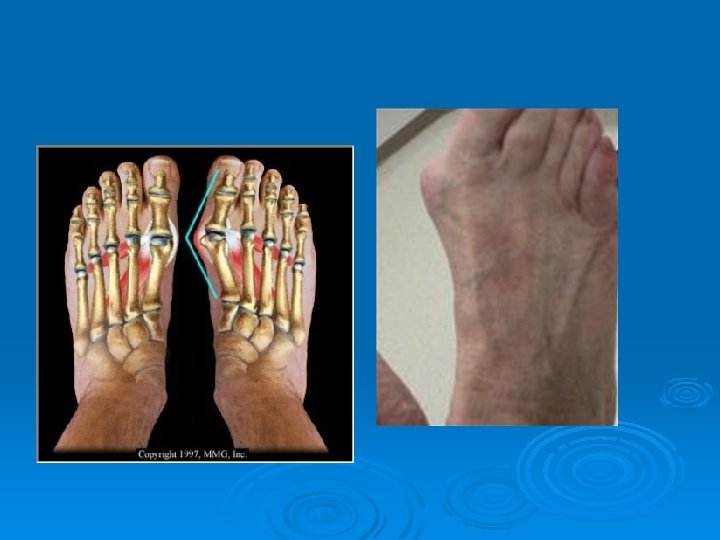

Bunion / Hallux Valgus Ø MX: l Ø S/S: l Ø Obvious deformity, tenderness, and swelling TX: l Ø Bony enlargement of the head of the 1 st metatarsal caused from wearing improperly fitting shoes Proper shoe selection, protection devices, surgery may be necessary Prevention: l Properly fitting shoes